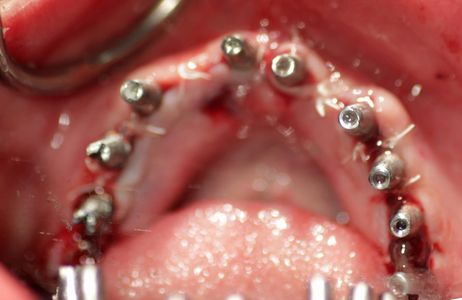

Dr. Gibney surgically implants 10 posts on the top and then 10 posts on the bottom.

After surgery, Dr. Gibney takes CAT scan images and impressions to review the implant surgery and create her temporary teeth. Immediately after, Cristina is sent home to rest.